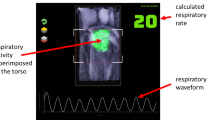

A depth camera measures the distance to the surface of all objects within its field of view (FOV) and outputs a single matrix of distances (or depths) for each image frame. A respiratory volume (RV) signal was generated from the depth data image sequences by integrating the change in depths across a region of interest defined on the subject’s chest region over time (i.e. frame-by-frame). Figure 1 shows the subject in the depth image with the ROI shown defined on the torso during one of the experiments. ROIs may be generated in several ways. The simplest is to use the whole depth image. Alternatively, the user can define a box around the chest region. More sophisticated methods may be used to automate the ROI placement. The ROI generated in Fig. 1 uses a flood fill method. The RV signal was generated by integrating changes in depths across the area defined within the ROI over time. Figure 2 shows an example of one of the RV signals generated during the study where the identified peaks and troughs are indicated. These were determined using a peak detection algorithm. We calculated respiratory rate using the peak-to-peak breath periods extracted from the RV signal and a tidal volume (TV) from the peak-to-trough changes in volume extracted from the RV signal. The algorithm for calculating RR and TV is shown schematically in the flow diagram of Fig. 3. Reference signals for respiratory rate and tidal volume were obtained from the ventilator. These were synchronized with the output from the depth-sensing algorithm and used in the performance analysis. Note that data was analysed when both RR and TV were available as RR took slightly longer to begin reporting due to its additional low pass filter smoothing (usually a few seconds later than tidal volume which was computed breath-to-breath). This additional low pass filter is shown in Fig. 3. In this way we matched our results temporally.